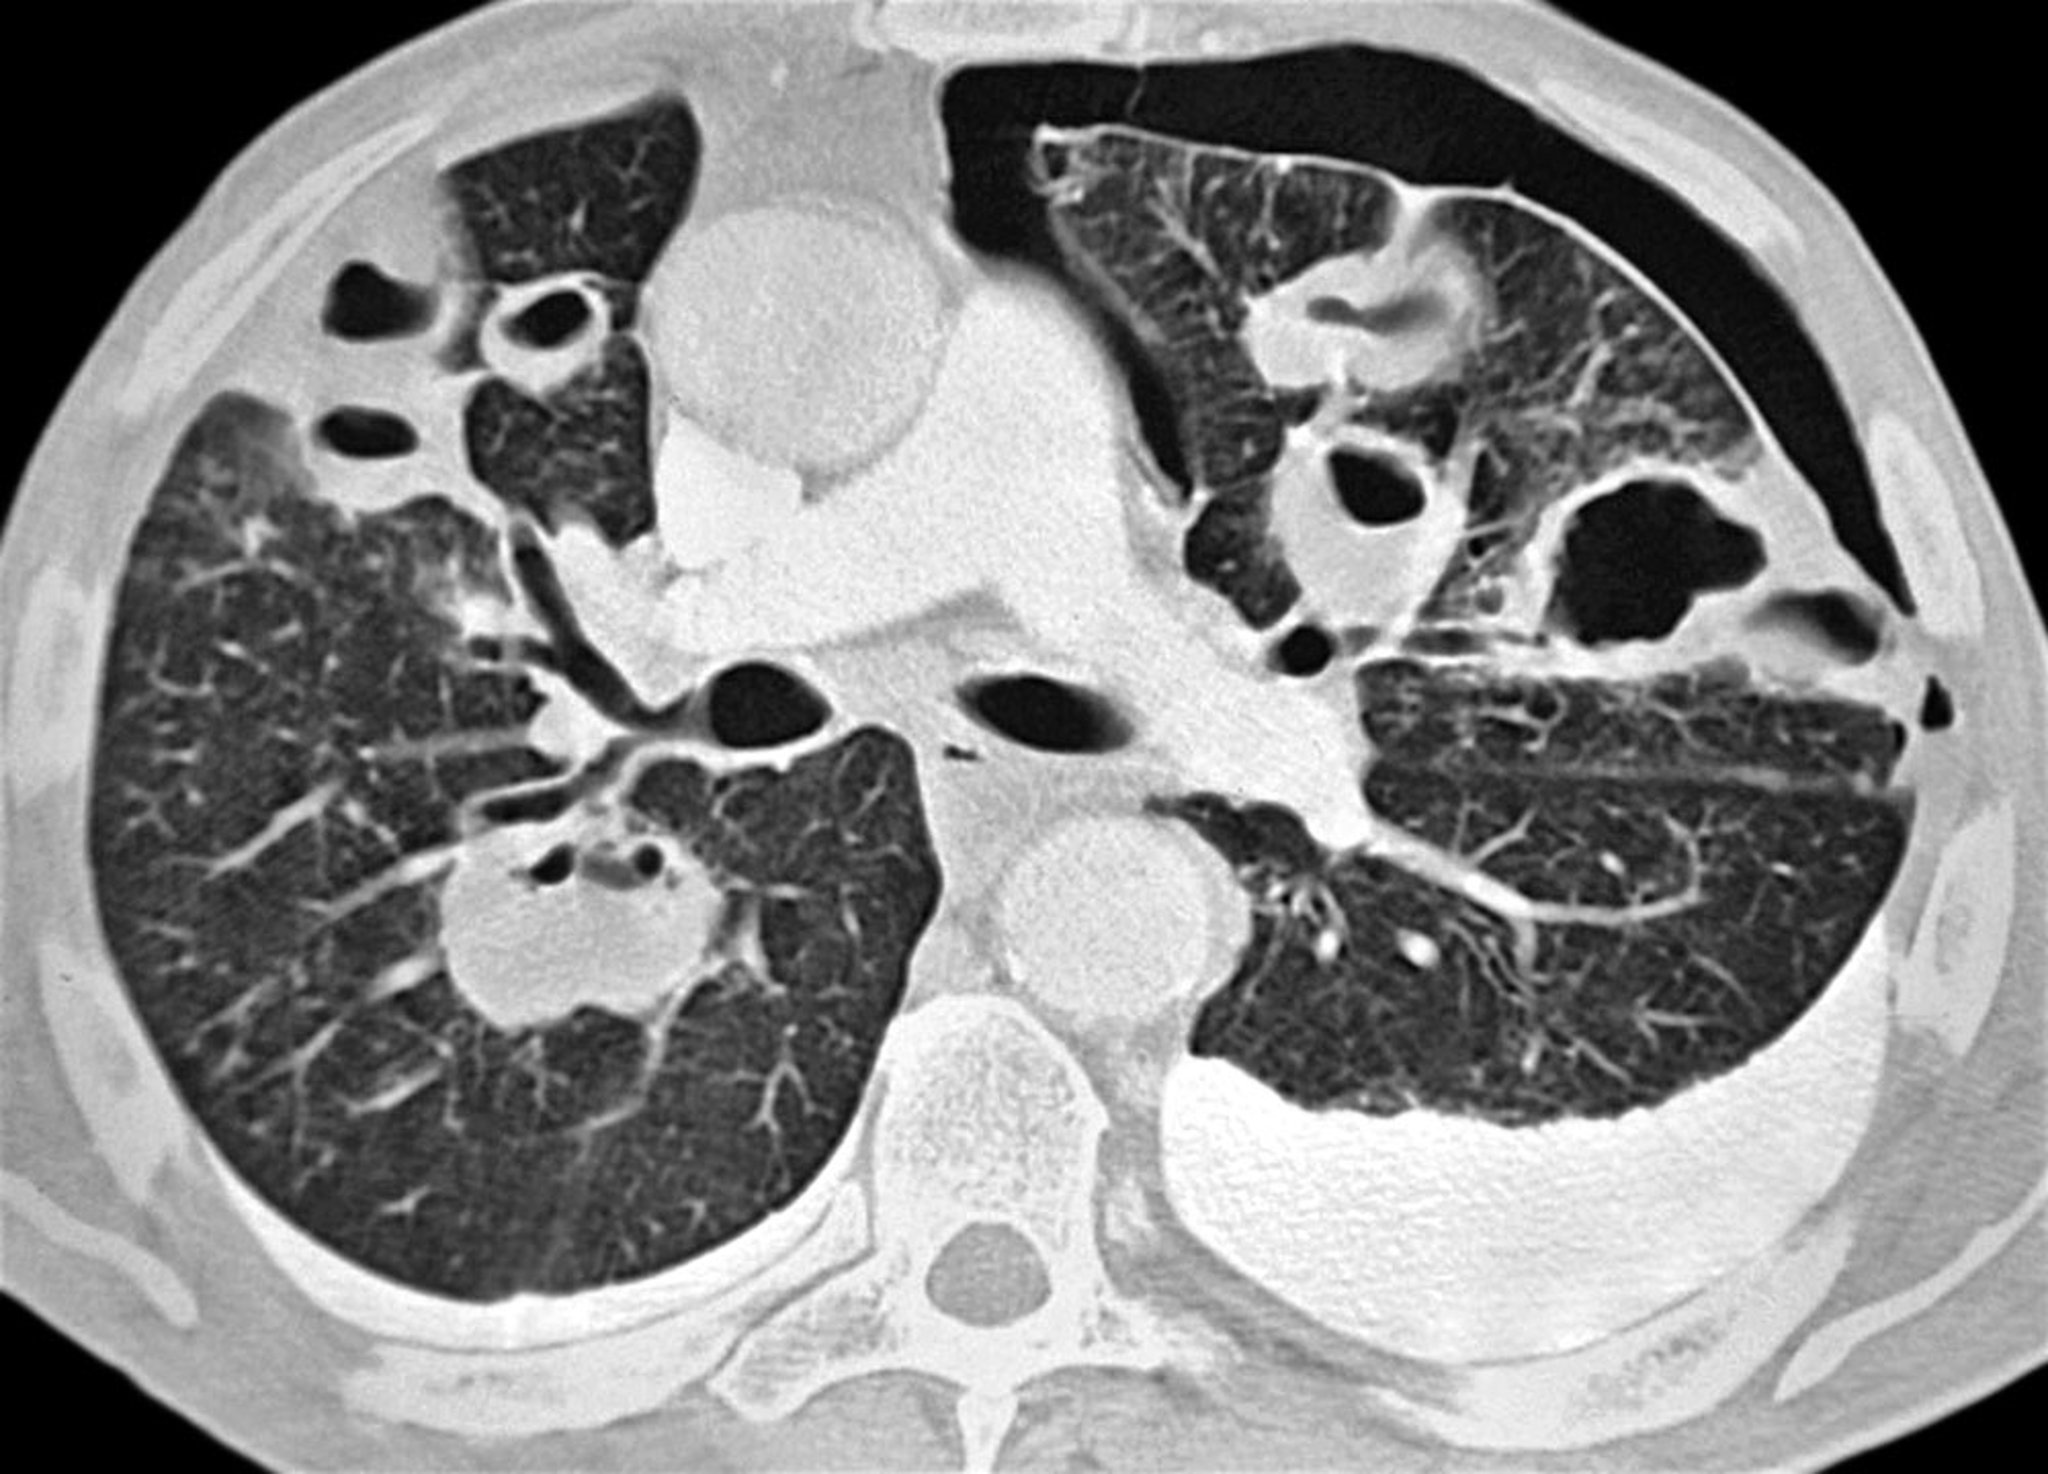

The diagnosis is suspected in patients whose condition is stable but who have dyspnea or pleuritic chest pain and is usually confirmed with upright inspiratory chest radiograph. The density of the lung tissue is increased if expiratory films are obtained, thereby increasing the difference in contrast between the air in the pleural space and the adjacent lung tissue (which has less air due to a combination of the expiratory state and any collapse). Radiolucent air and the absence of lung markings juxtaposed between a shrunken lobe or lung and the parietal pleura are diagnostic of pneumothorax. Tracheal deviation and mediastinal shift are seen with large pneumothoraces. The diagnosis may also be made using bedside ultrasound if underlying lung disease does not prevent adequate visualization.

Small pneumothoraces (eg, < 10%) are sometimes overlooked on chest radiograph. In patients with possible pneumothorax, lung markings should be traced to the edge of the pleura on chest radiograph. Even large pneumothoraces may not be evident on supine radiographs, and the deep sulcus sign (an abnormally deep costophrenic angle) should be specifically looked for, as it may be the only sign of pneumothorax on the radiograph in a supine patient. Conditions that mimic pneumothorax radiographically include emphysematous bullae, skinfolds, folded bed sheets, and overlap of stomach or bowel markings on lung fields.

CT scan also allows excellent visualization of pneumothoraces and related pathology in supine patients.